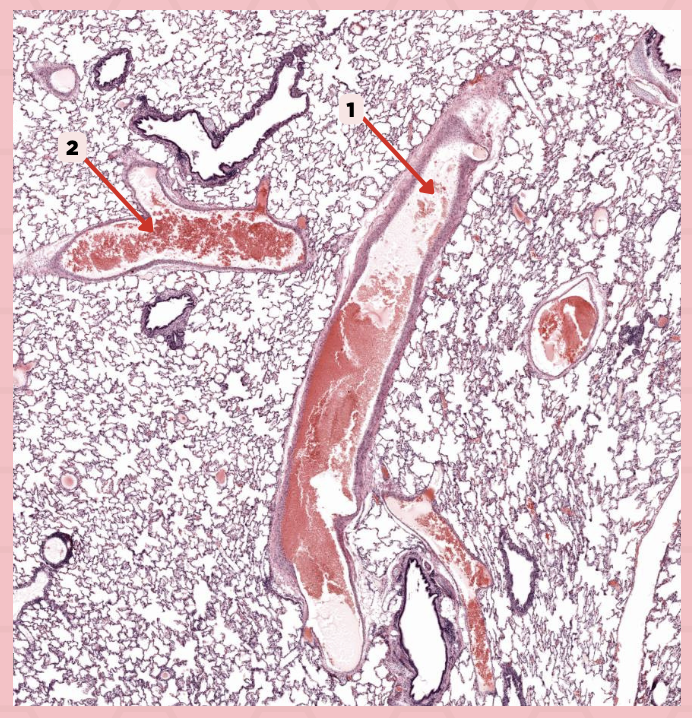

Bigger and smaller intrapulmonary bronchi

What are the two types of intrapulmonary bronchi?

Pseudostratified epithelium (bigger bronchioles), Simple columnar or cuboidal (smaller)

What are the types of epithelium in No. 3?

Interalveolar septa

Identify the structure labeled as 1.

Intrapulmonary bronchi

Identify the structure labeled as 2.

Bronchiole

Identify the structure labeled as 3.

Terminal bronchiole

Identify the structure labeled as 4.

Respiratory bronchiole

Identify the structure labeled as 5.

Alveolar ducts

Identify the structure labeled as 6.

Alveolar sacs

Identify the structure labeled as 7.

Deoxygenated blood

What type of blood does vessel No. 1 carry?

Connective tissue septae

Where would No. 2 be located?

Pulmonary artery

Identify the structure labeled as 1.

Tributary of pulmonary vein

Identify the structure labeled as 2.

Oxygenated blood

What type of blood does this vessel supply?

Bronchial artery

Identify the structure labeled as 1.